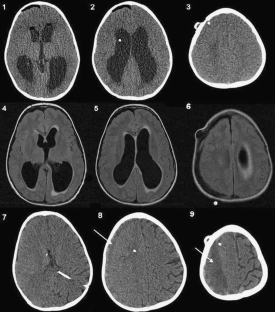

Fig. 2